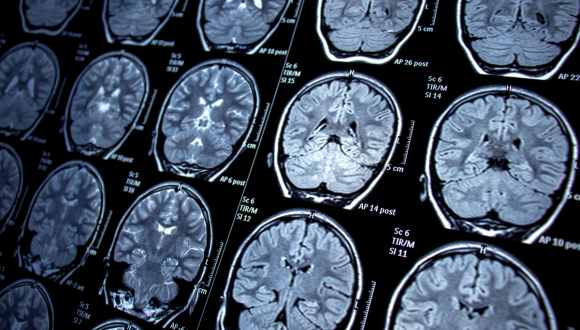

Modeling neurological disorders using patient-specific iPSCs